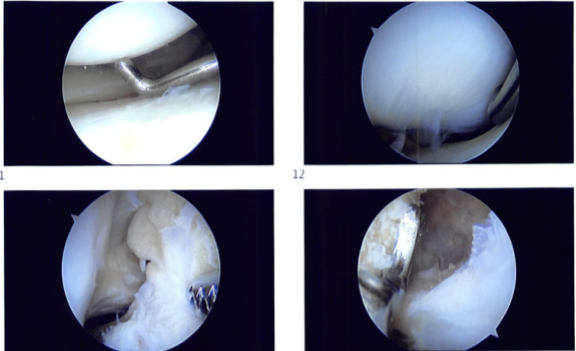

Introperative images

The arthroscope was inserted through a lateral anterior portal created by a lateral parapatellar incision. The patellofemoral compartment was found to have complete cartilage. The meniscus and cartilage in the medial patellofemoral compartment were found to be intact.

The anterior condyle notch was examined and found to be devoid of ACL from the proximal connection. The lateral tibiofemoral compartment was examined and found to have intact cartilage with degenerative tearing and across the margin of the lateral meniscus with no debridement because the meniscus was intact.

To remove the ACL stump and prepare the medial surface of the lateral femoral condyle at the intercondylar region for the bone graft, the intercondylar notch was debrided. In the preparation phase, a shaver and a coblation wand were employed.

The graft was examined and there was no evidence of impingement. Sutures were placed beneath the skin. After extensively irrigating the knee, the final photographs were stored. The wounds were closed with 2-0 Vicryl and 3-0 Monocryl. Dressing was done using Adaptic and Dermabond, Steri-Strips, 4 x 4, ABD, Webril, and ACE wrap. A knee immobilizer was worn. In stable condition, the patient was extubated and brought to the recovery room.